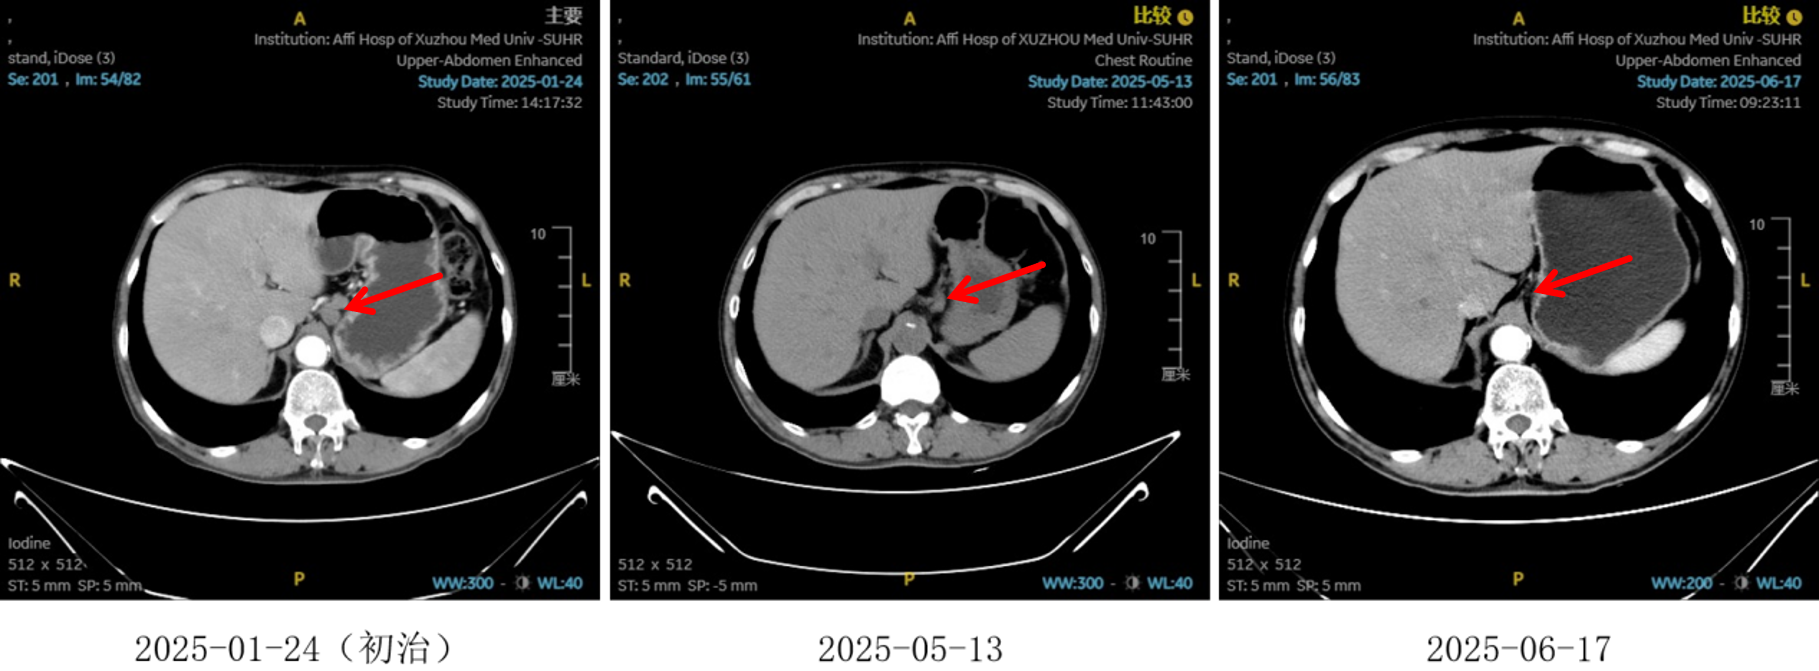

2025-01-22:患者行胃镜及病理检查确诊为食管鳞状细胞癌,CT提示病变位于胸中下段,伴纵隔、左肺门及胃小弯旁多发淋巴结转移,临床分期为cT4N2M0,属于局晚期食管癌。

图1:初治影像学 [图左:食管胸中下段管壁增厚,强化不均,较厚处管壁约17mm,边缘模糊,病灶局部与邻近大血管、气管壁分界不清。图右:纵隔内(3P、4、7)、左肺门及胃小弯旁示多发增大淋巴结影,部分融合,强化不均,较大者大小约18mm×15mm。]

图2:2周期化疗联合抗血管治疗后食管癌病灶对比

图3:2 周期化疗联合抗血管治疗后淋巴结对比

图5:4、6周期化免靶后食管癌病灶对比

图6:4、6周期化免靶后淋巴结对比

疗效评估

治疗2周期后,食管壁厚度由17mm降至15mm,淋巴结由18mm×15mm缩小至16mm×13mm;4周期后,食管壁进一步缩至12mm,淋巴结明显减少;6周期后,食管壁仅余10mm,纵隔内仅见小淋巴结影,疗效评估“接近CR”。